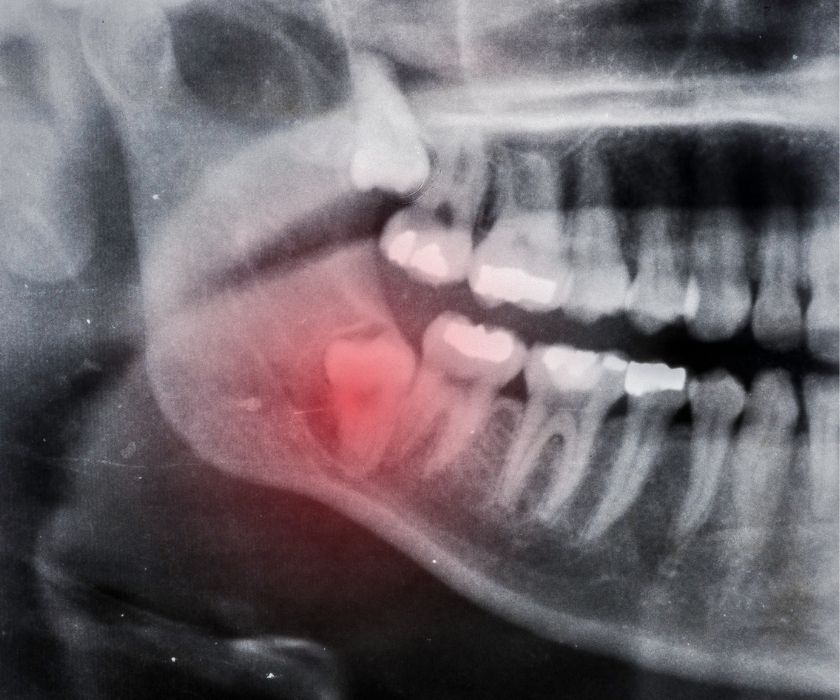

Triệu chứng của răng khôn mọc ngầm

Triệu chứng của răng khôn mọc ngầm

Bước 1: Thăm khám và chụp X-quang

Bác sĩ kiểm tra tổng quát, chụp phim X-quang để đánh giá vị trí, hướng mọc và mức độ ảnh hưởng của răng khôn.